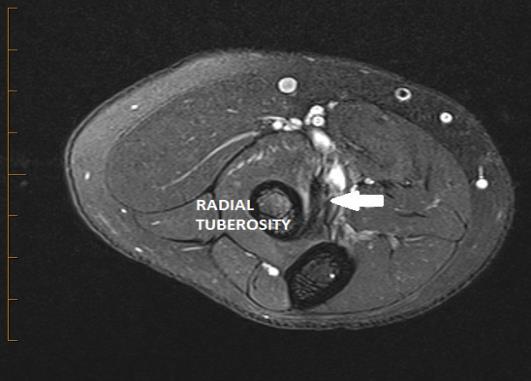

Fig. 1 Ultrasound showing a normal distal biceps tendon inserting at the radial tuberosity.

Fig. 6 Axial MRI showing a normal low signal biceps tendon inserting at the radial tuberosity.